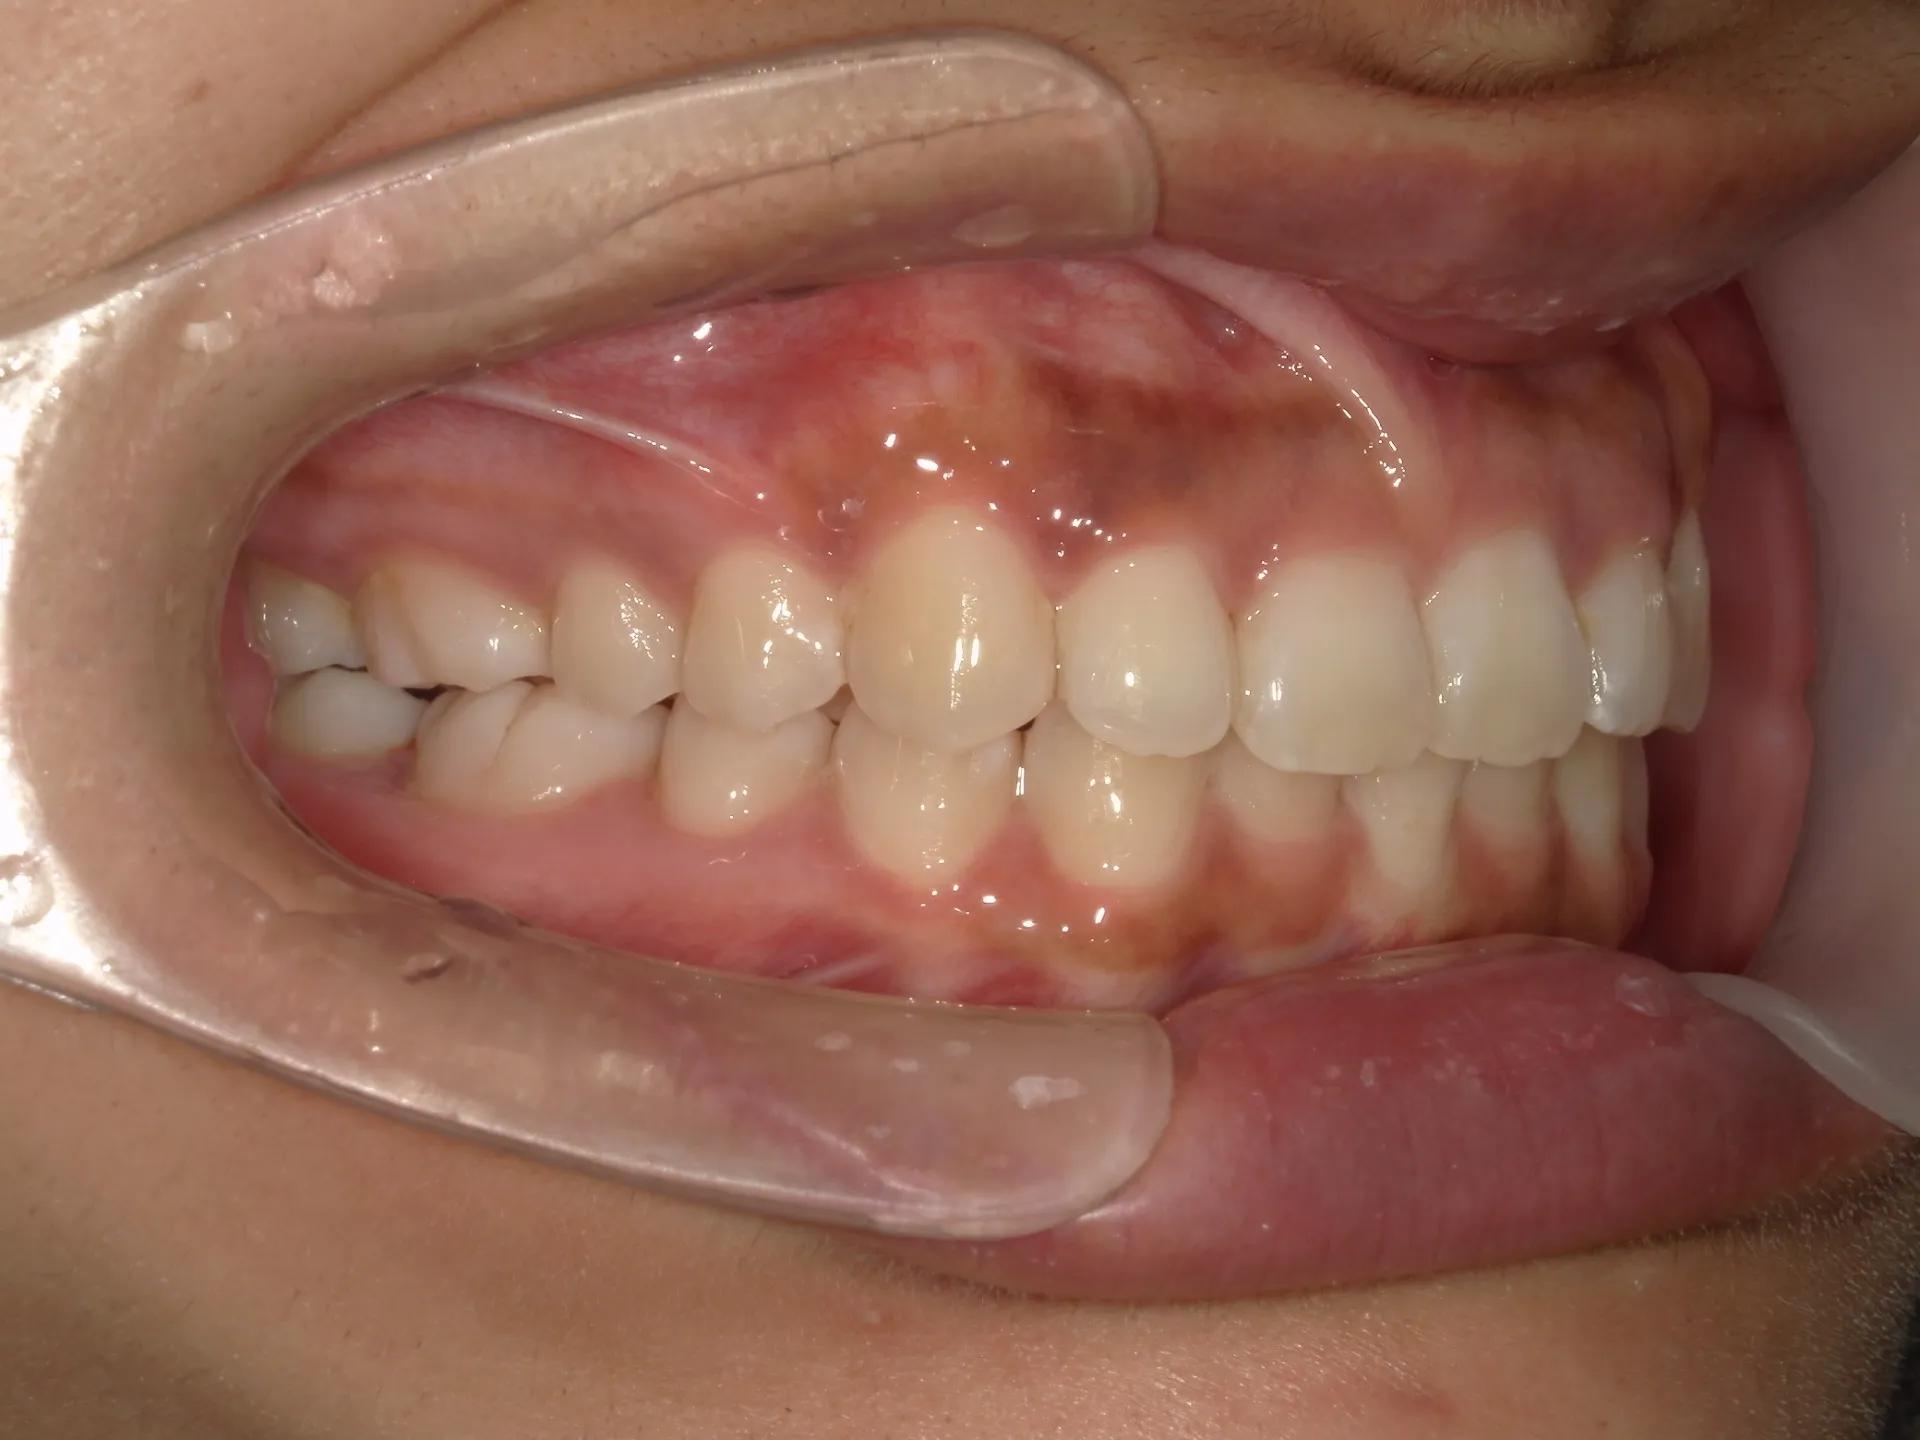

内側に倒れた前歯を矯正で正す!

前歯が内側に倒れてたりしませんか?

または2番目の歯が外側に飛び出していませんか?

この2つはよく同時に起こることがあります。

今回はインビザライン矯正治療(マウスピース矯正)で治療した症例についてご紹介いたします。